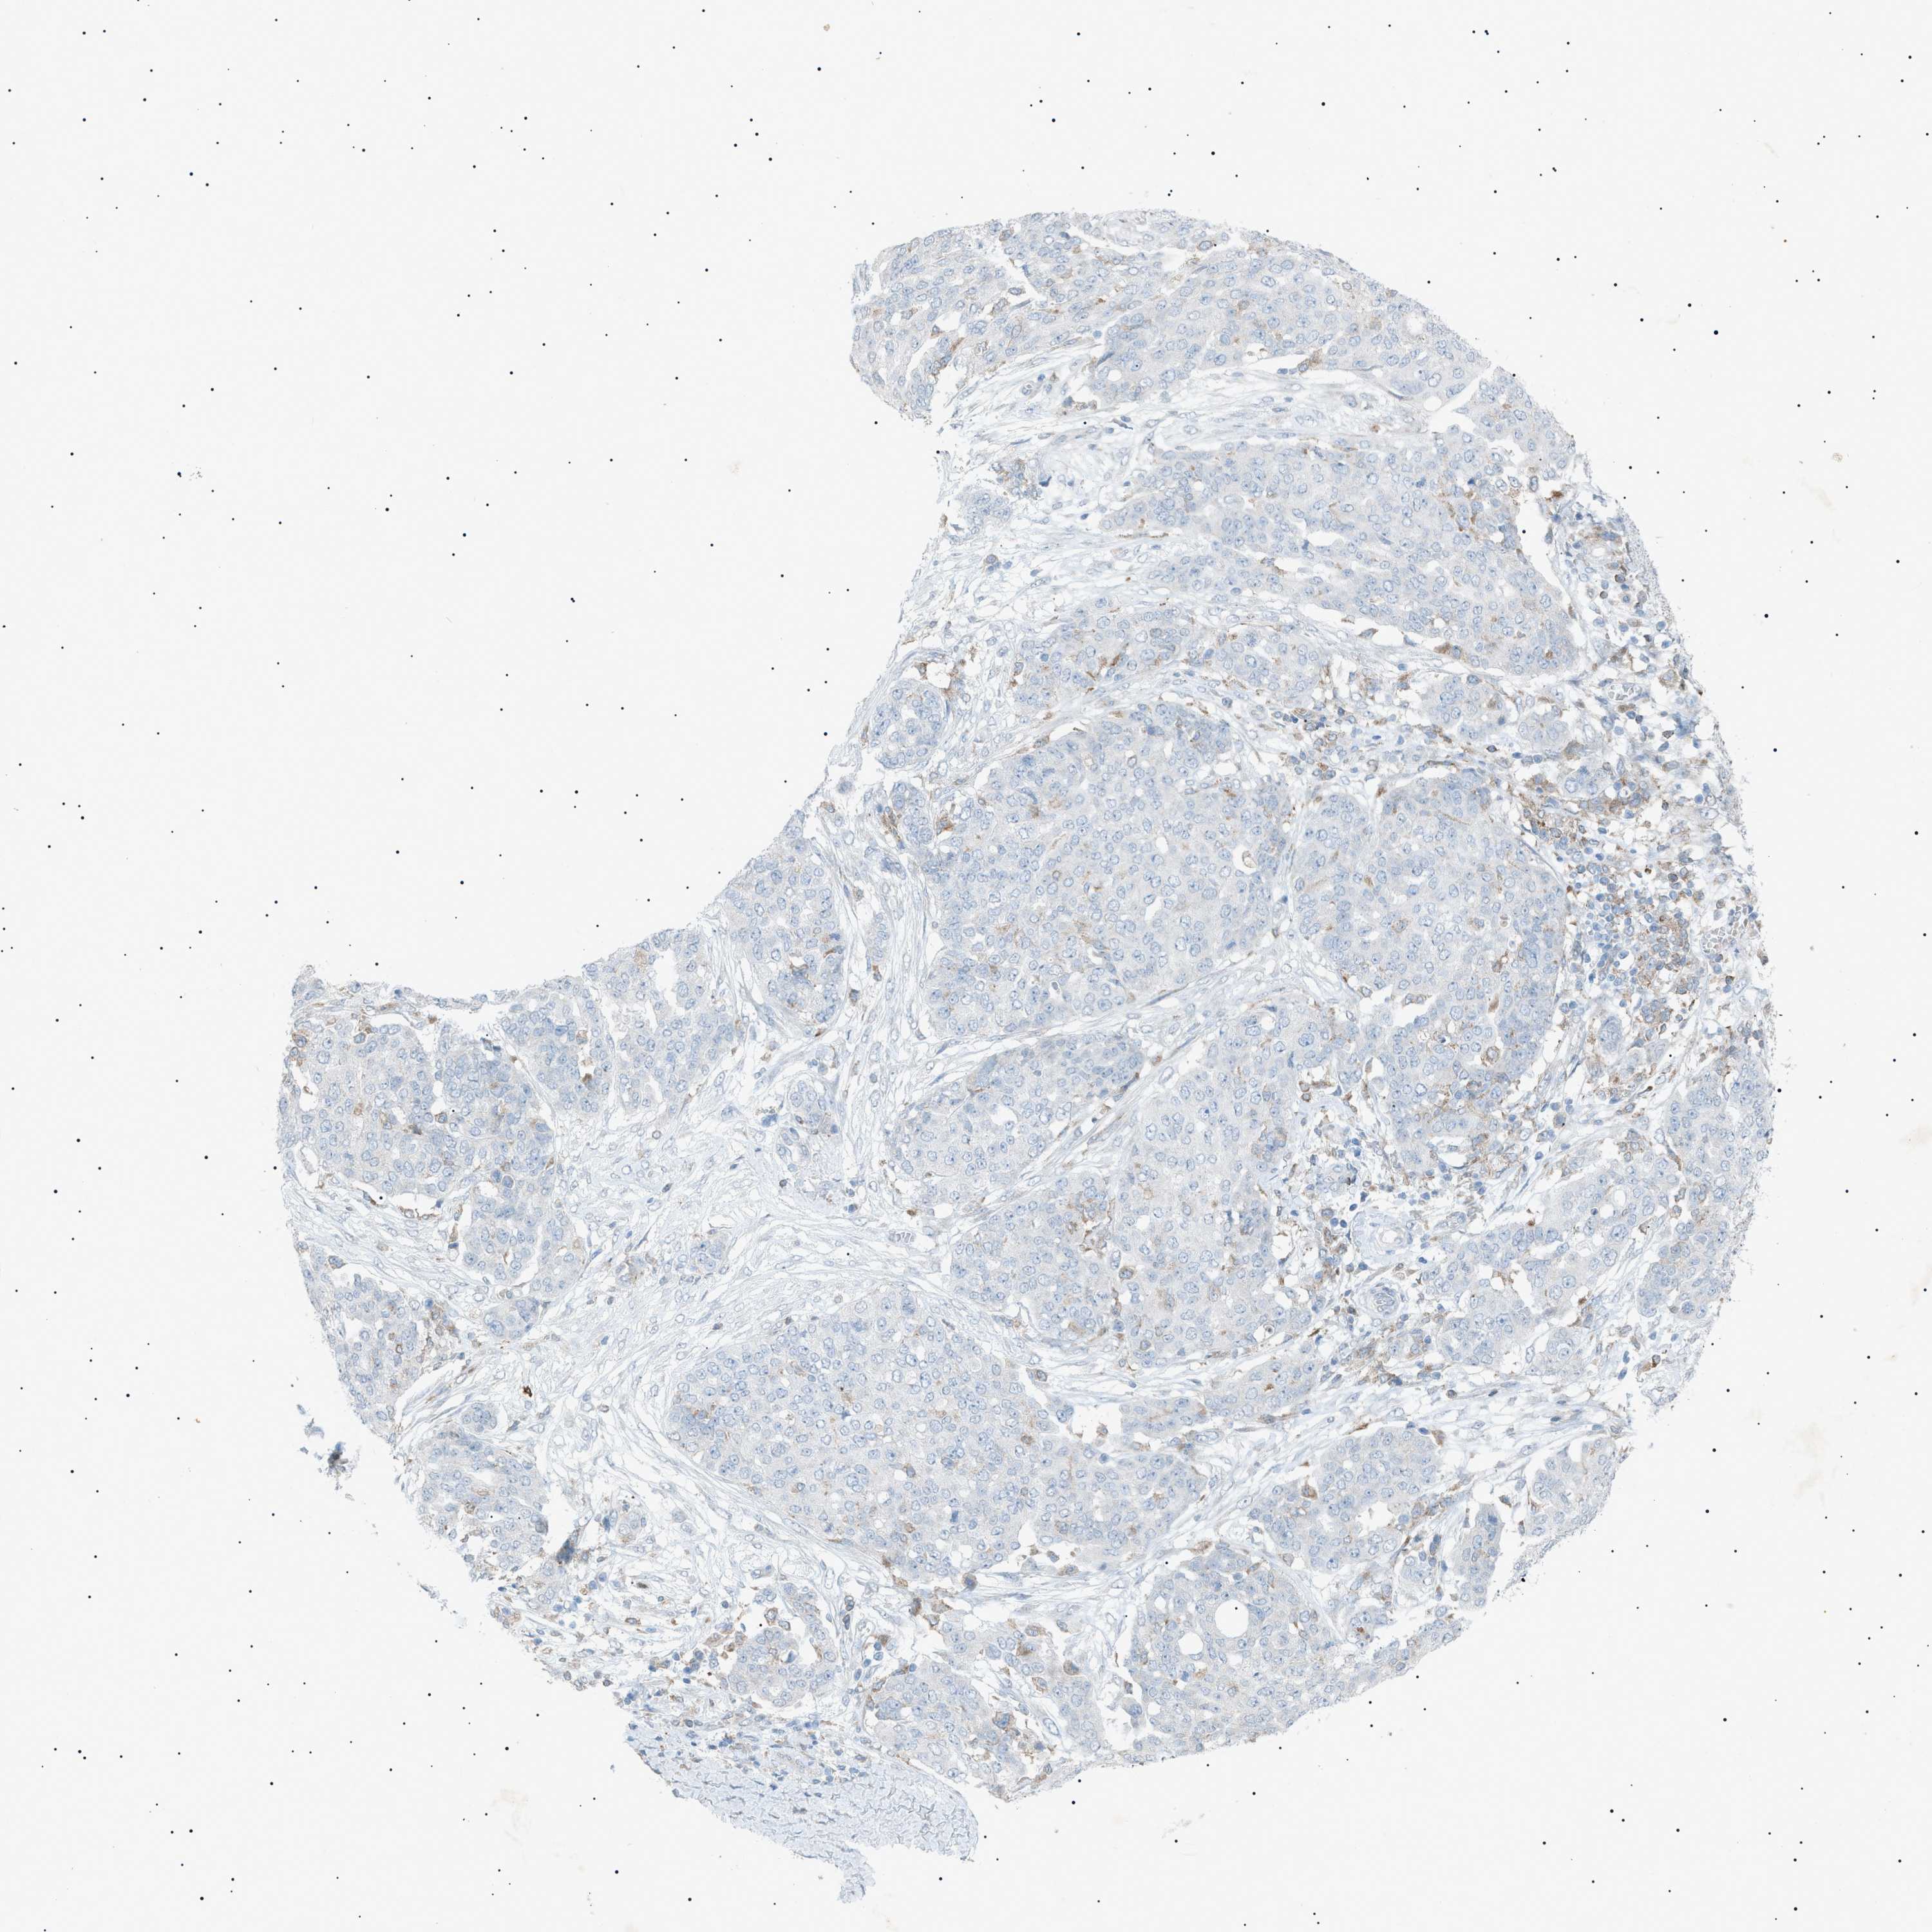

OVARIAN CANCER - Protein expressioni

A mouse-over function shows sample information and annotation data. Click on an image to view it in a full screen mode. Samples can be filtered based on level of antibody staining by selecting one or several of the following categories: high, medium, low and not detected. The assay and annotation is described here.

Note that samples used for immunohistochemistry by the Human Protein Atlas do not correspond to samples in the TCGA dataset.

Antibody stainingi

Antibody staining in the annotated cell types in the current human tissue is reported as not detected, low, medium, or high, based on conventional immunohistochemistry profiling in selected tissues. This score is based on the combination of the staining intensity and fraction of stained cells.

Each image is clickable and will lead to virtual microscopy that enables deeper exploration of all samples and also displays staining intensity scores, fraction scores and subcellular localization as well as patient and tissue information for each sample.

Antibody HPA001198

Antibody HPA002028

Antibody CAB016689

Antibody CAB080300

Cystadenocarcinoma, mucinous, NOS

Carcinoma, endometroid

Cystadenocarcinoma, serous, NOS

Carcinoma, NOS